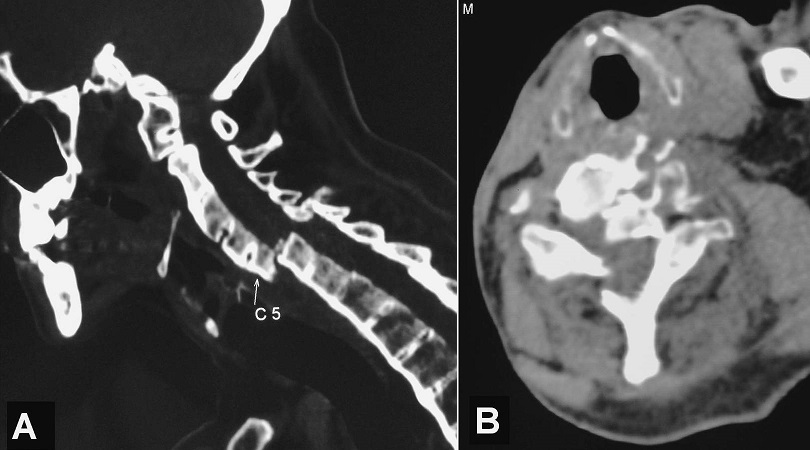

A 59-year-old man with a history of chronic ankylosing spondylitis for many years, developed neck pain and left cervico-brachial neuralgia following a road traffic accident sustained one week before. Plain radiographs of cervical spine were initially misinterpreted. On examination, he had severe neck pain on mobilization without any neurological deficits. Delayed cervical computed tomography scan showed ossification of the anterior longitudinal ligament, calcification of the intervertebral discs and complete vertebral fusion (so called bamboo spine) with transversal fracture at C5-C6 disc level (so called carrot-stick fracture) causing a luxation of the cervical spine with significant compromise in canal space (A and B). A transcranial spinal traction was performed followed by anterior decompression and stabilization via an anterolateral cervical approach. The outcome was favourable. Transverse fractures of the spine are rare in patients with ankylosing spondylitis and diagnosis should be considered following even minor trauma. These atypical unstable fractures occur because of the loss of flexibility and fragility of the osteoporotic spine. Early diagnosis for possible intervention is important because of the high mortality rate.